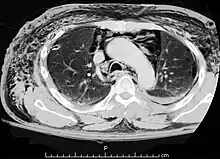

A CT scan showing air in the mediastinum

Pneumomediastinum is uncommon and occurs when air leaks into the mediastinum. The diagnosis can be confirmed via chest X-ray showing a radiolucent outline around the heart and mediastinum or via CT scanning of the thorax.